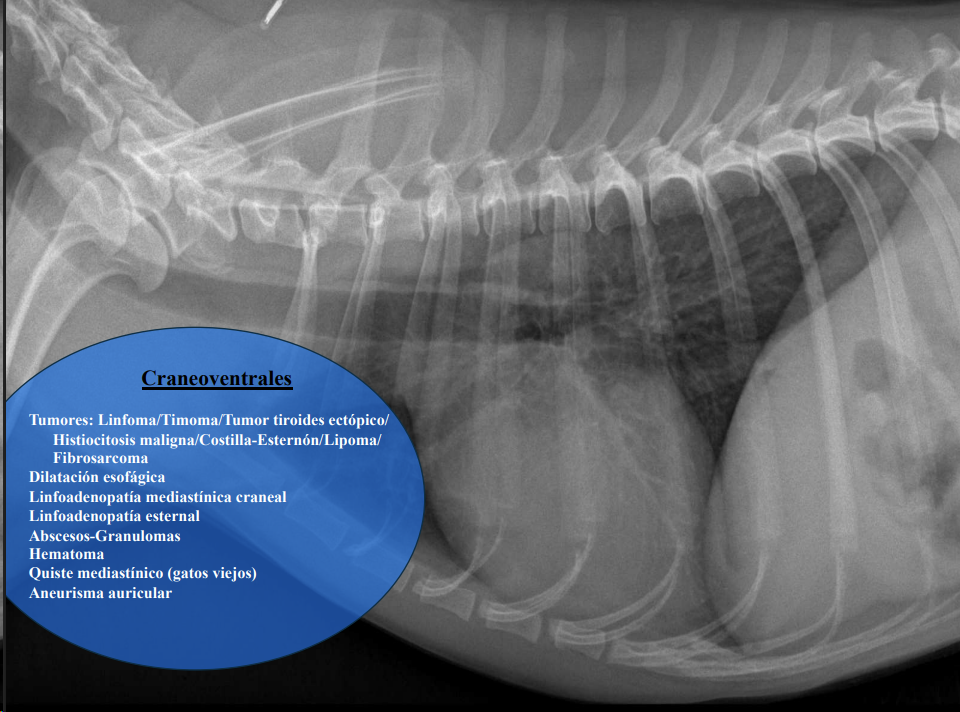

-

Craneoventrales: linfoma, timoma, tumor tiroideo, histiocitosis, lipoma, fibrosarcoma, linfoadenopatía esternal o craneal, absceso, aneurisma auricular.